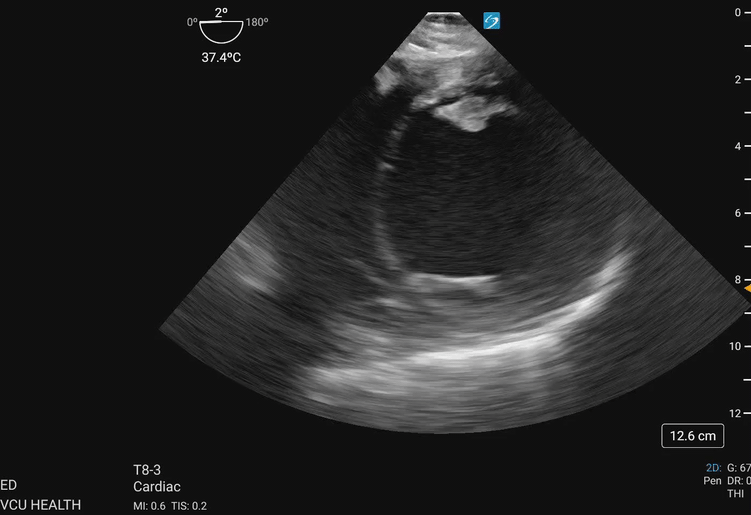

Figure 2. Transgastric midpapillary view demonstrating the left ventricle and papillary muscles visualized at approximately 40cm depth from the incisions, omniplane between 0-20 degrees, and anteflexion of the probe. This patient demonstrates global left ventricular hypokinesis. Image courtesy of Lindsay Taylor, MD.

Figure 3a. Walls of the left ventricle as seen on TGSAX with vascular territories. The left ventricle here demonstrates global hypokinesis rather than pathology isolated to one vascular territory. Image courtesy of Lindsay Taylor, MD.